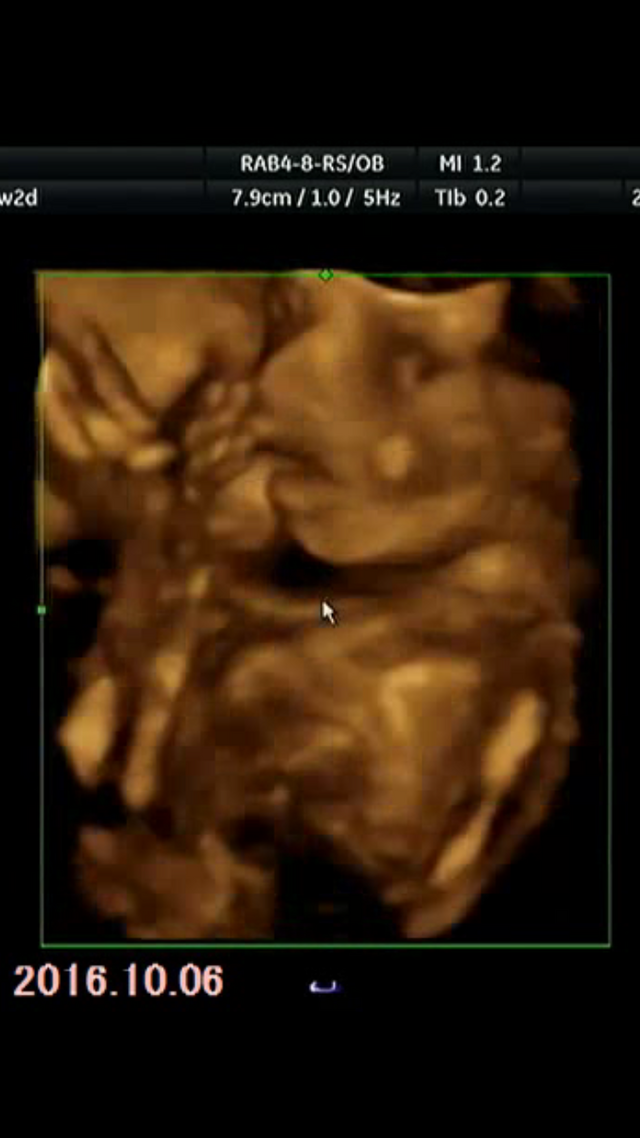

20週0日(20w0d・男の子)|piiiii さん(30歳)

エコー写真撮影時のエピソード:

妊娠悪阻と脱水、早期前期破水、低地胎盤、絨毛膜下血腫、切迫流産… 初期からつらい入院生活。毎日不安で不安で仕方なかったのですが、赤ちゃんの元気な姿をエコーで見ることだけが私の癒し。

いつもは恥ずかしがってお顔を手で隠したりしてたのですが、この時『こっち向いてー』と言ったらお顔を見せてくれました!まだ20週なのではっきりお顔の形は分かりませんが、本当にうれしい瞬間でした!